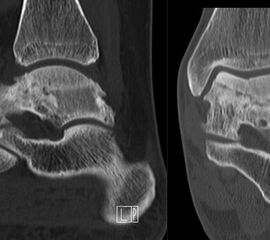

Abbildung 2.1.

Bildbeispiele symptomatische OCL

Zum Lesen der Bildbeschreibung und zur Vollansicht bitte das Bild anklicken. Bild: H. C. Rischke

Abbildung 2.2.

Bilder eines Patienten mit Z. n. mehrfachen Sprunggelenksdistorsionen in der Vergangenheit, besonders heftige Distorsion des linken Sprunggelenkes 5 Wochen vor der Untersuchung. Die SPECT/CT zeigt eine instabile osteochondrale Läsion mit deutlicher Aktivierung.

Abbildung 2.3.

Klärung bei Schmerzen im rechten OSG bei OCL an der medialen Talusschulter. Z. n. OSG-Distorsion vor 2 Jahren und Z. n. OSG-Fraktur / Syndesomosenruptur. Ausgedehnte OCL, hier jedoch kein erhöhter Knochenmetabolismus; lediglich Nachweis einer Stressreaktion im Bereich der Synchondrose eines Os trigonum als Schmerzursache.